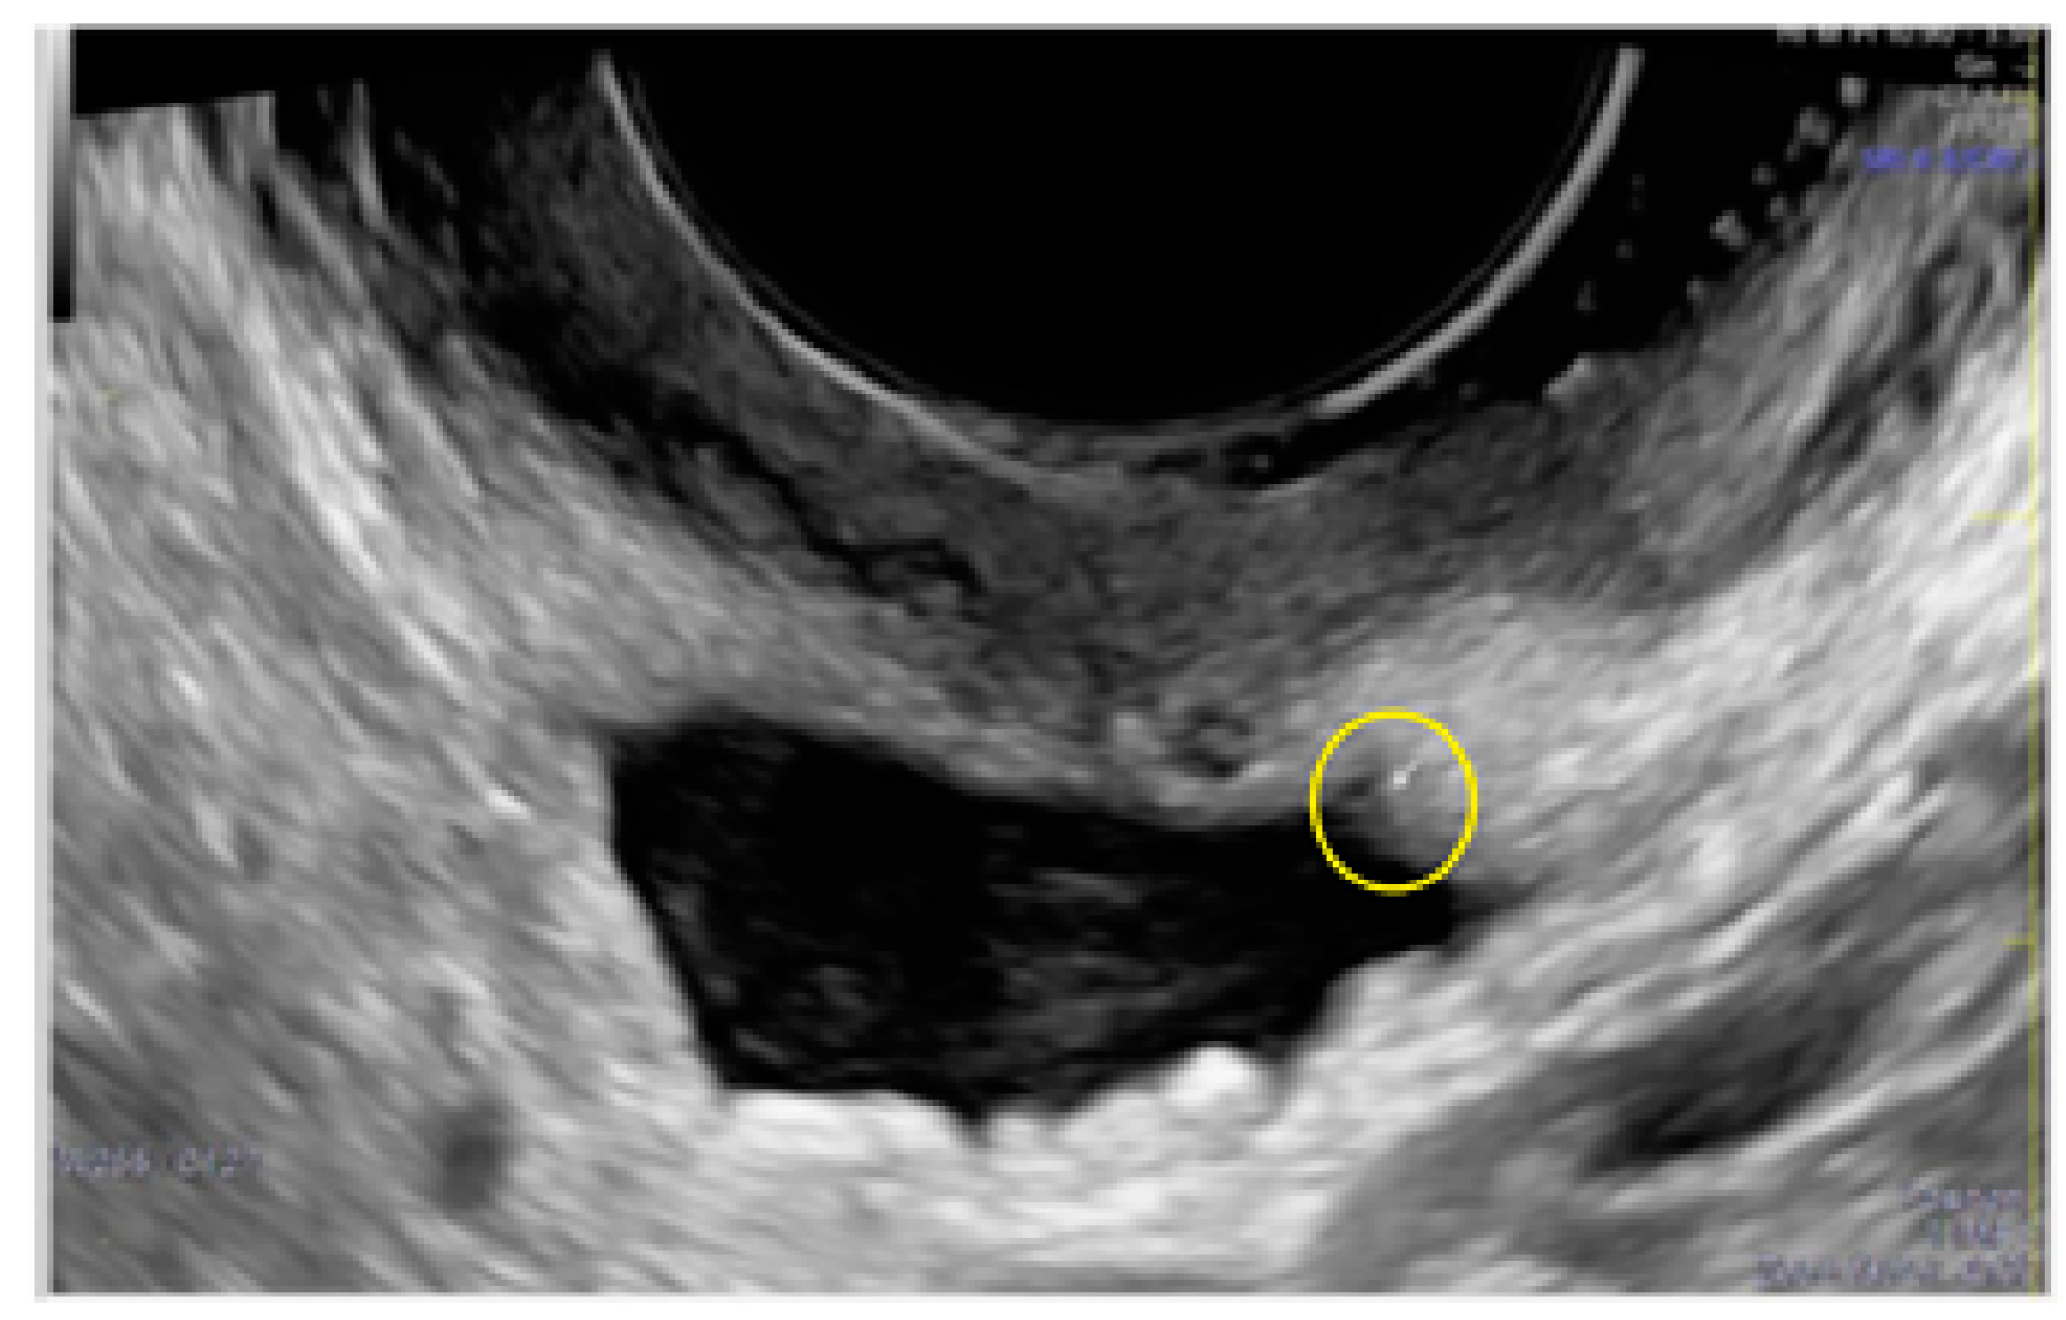

- The presence of hypoechogenic associated tissue (hypoechoic areas surrounding a small cyst area; we called this a “hat”). This tissue does not protrude or invaginate the peritoneal surface.

- The lesion may be convex, protruding from the peritoneal surface into the peritoneal cavity (we called this “bulging”), or it may appear as a concave defect in the peritoneum (we called this a “pocket”).

- The presence of hyperechoic foci (we called this a “pearl”).

- The presence of velamentous (filmy) adhesions associated to the lesion (we called this a “veil”).

3.3. Cystic Lesions Arranged in a Cluster